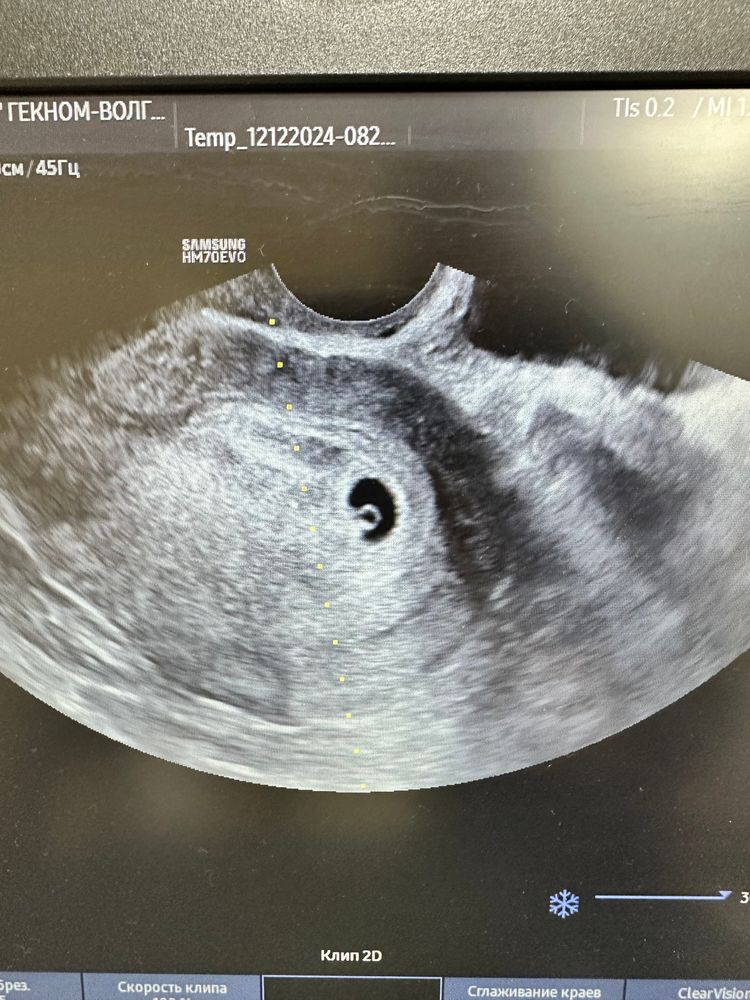

Сходила на УЗИ

Елизавета, 8мм пя, жм 2,5мм. Сама гинеколог сказала что думала что увидит только ПЯ

Наталья, по месячным 6.4, а по узи 5.4, это потому что у меня была поздняя овуляция на 21 дц (отслежана этим же врачом). Поэтому разница в неделю

УЗИ на 28 дц Узи в 6,6 недель ♥️